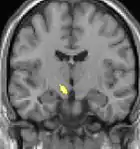

Hypothalamus

La théorie selon laquelle les AVF proviendraient d'une anomalie dans l'hypothalamus[48] est une des plus acceptées ; le Dr Peter James Goadsby[49], spécialiste australien a développé cette théorie. Cette thèse pourrait expliquer pourquoi les maux de tête se produisent avec une chronologie précise et régulière. L'un des rôles de l'hypothalamus est de réguler le rythme circadien. Des anomalies métaboliques ont d'ailleurs été signalées chez des patients.

![]() | ![]() | ![]() |

| La tomographie par émission de positons (TEP) montre les zones du cerveau étant activées durant la douleur | ||

| La morphométrie voxel par voxel (VBM) montre les différences structurelles des zones du cerveau | ||

Les images par tomographie à émission de positron indiquent les régions du cerveau qui sont activées lors de la douleur, par rapport aux périodes sans douleur. Elles montrent les régions du cerveau qui sont toujours actives durant la douleur en jaune/orange (appelé "matrice-douleur"). La zone au centre (dans les trois vues) est spécifiquement activée uniquement pendant la crise. Les photos sur la ligne du bas (effectuées par VBM) montrent les différences structurelles entre les patients souffrant d'AVF et des personnes saines : seulement une partie de l'hypothalamus est différente[50],[51].

Il semble exister des anomalies microstructurales hypothalamiques bilatérales (en l'occurrence l'existence d'une hypertrophie)[52] sans que l'on sache si ces anomalies sont la cause ou la conséquence de la répétition des crises.